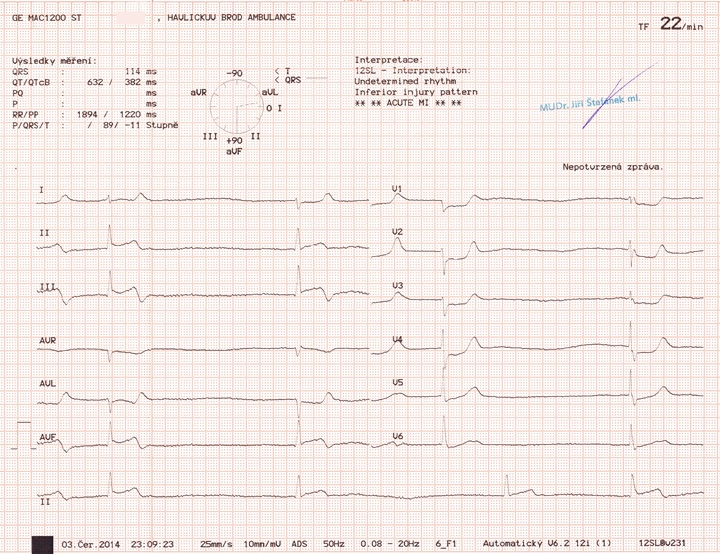

Pacient (cca 65 let, muž) byl přivezen RZP jako bolesti břicha a bradykardie. Pacient hypotenzní, imobilní. Na EKG je výrazně patologický nález. Štíhlé komplexy QRS nejsou předcházeny P vlnami, jde zřejmě o junkční rytmus s těžkou bradykardií. Kromě toho si povšimněme ST elevací II, III a aVF se zrcadlovými depresemi ST v hrudních svodech. Jde o STEMI infarkt spodní stěny komplikovaný junkční bradykardií s postupným přechodem do kardiogenního šoku - pacient zaléčen a stejnou RZP, která ho přivezla na ambulanci, ihned transportován do blízkého spádového kardiocentra. Zjištěn uzávěr větve pravé koronární tepny, pacient zachráněn.